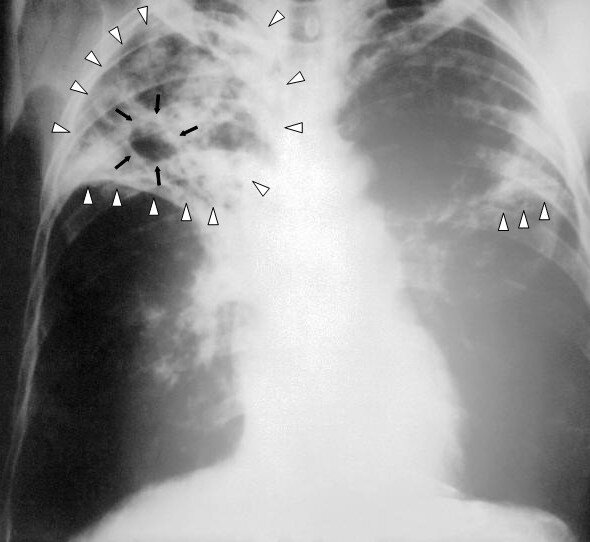

ТУБЕРКУЛЁЗ - широко распространённое в мире инфекционное заболевание человека. Туберкулёз обычно поражает лёгкие, реже затрагивая другие органы и системы.

Туберкулёз